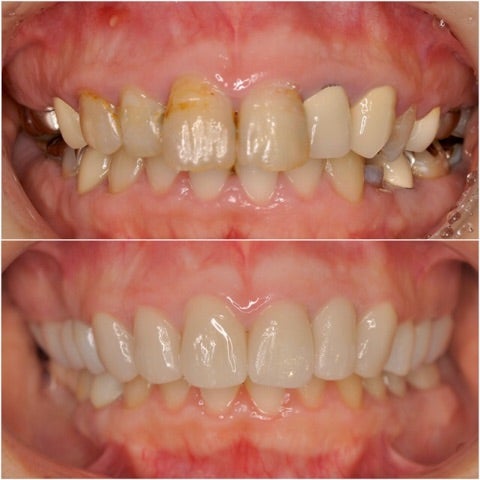

さて、本日は、噛み合わせが悪く、前歯が段々と前に出てきてしまっている事と、全体的に治療が古く、未治療の部分も多くどこから治して良いのか分からない。

▶︎写真ではわかりづらいのですが、前歯の前突に加え、虫歯や不良補綴物による見た目の審美障害を引き起こしています。

また、奥歯の噛み合わせが低く、所謂ディープバイトの状態で、前歯の前突(フレアーアウト)を引き起こしています。

写真左上の歯茎には根尖病巣による膿の出口も確認できます。

今回のケースは審美治療だけでなく、ディープバイトの改善や、保存不可能の部位にインプラント治療も行ったフルマウスの治療計画が必要となりました。

<治療後>

▶︎患者様のご希望により、全体的な見た目の改善と審美性の追求を行いました。

上顎の歯には全てジルコニアセラミッククラウンプレミアム¥220,000-/本

を使用し、《写真左下にはインプラントを2本埋入》しています。

ディープバイトの改善のため、スプリントを使用し、1mmのバイトアップも図っています。

▶︎奥歯のクラウンの高さが上がり、顎関節にも影響がないことを確認し、